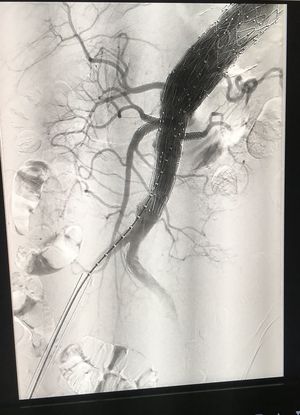

Angiografia, aorta addominale. Effettuata durante l’intervento dopo aver posizionato la protesi fenestrata.